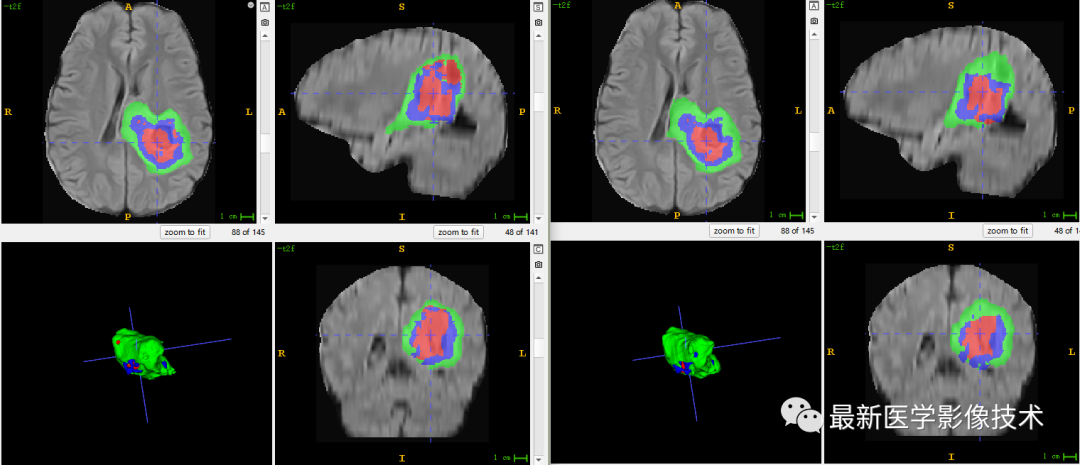

6、验证集分割结果

左图是金标准结果,右图是网络预测结果。

7、测试集分割结果